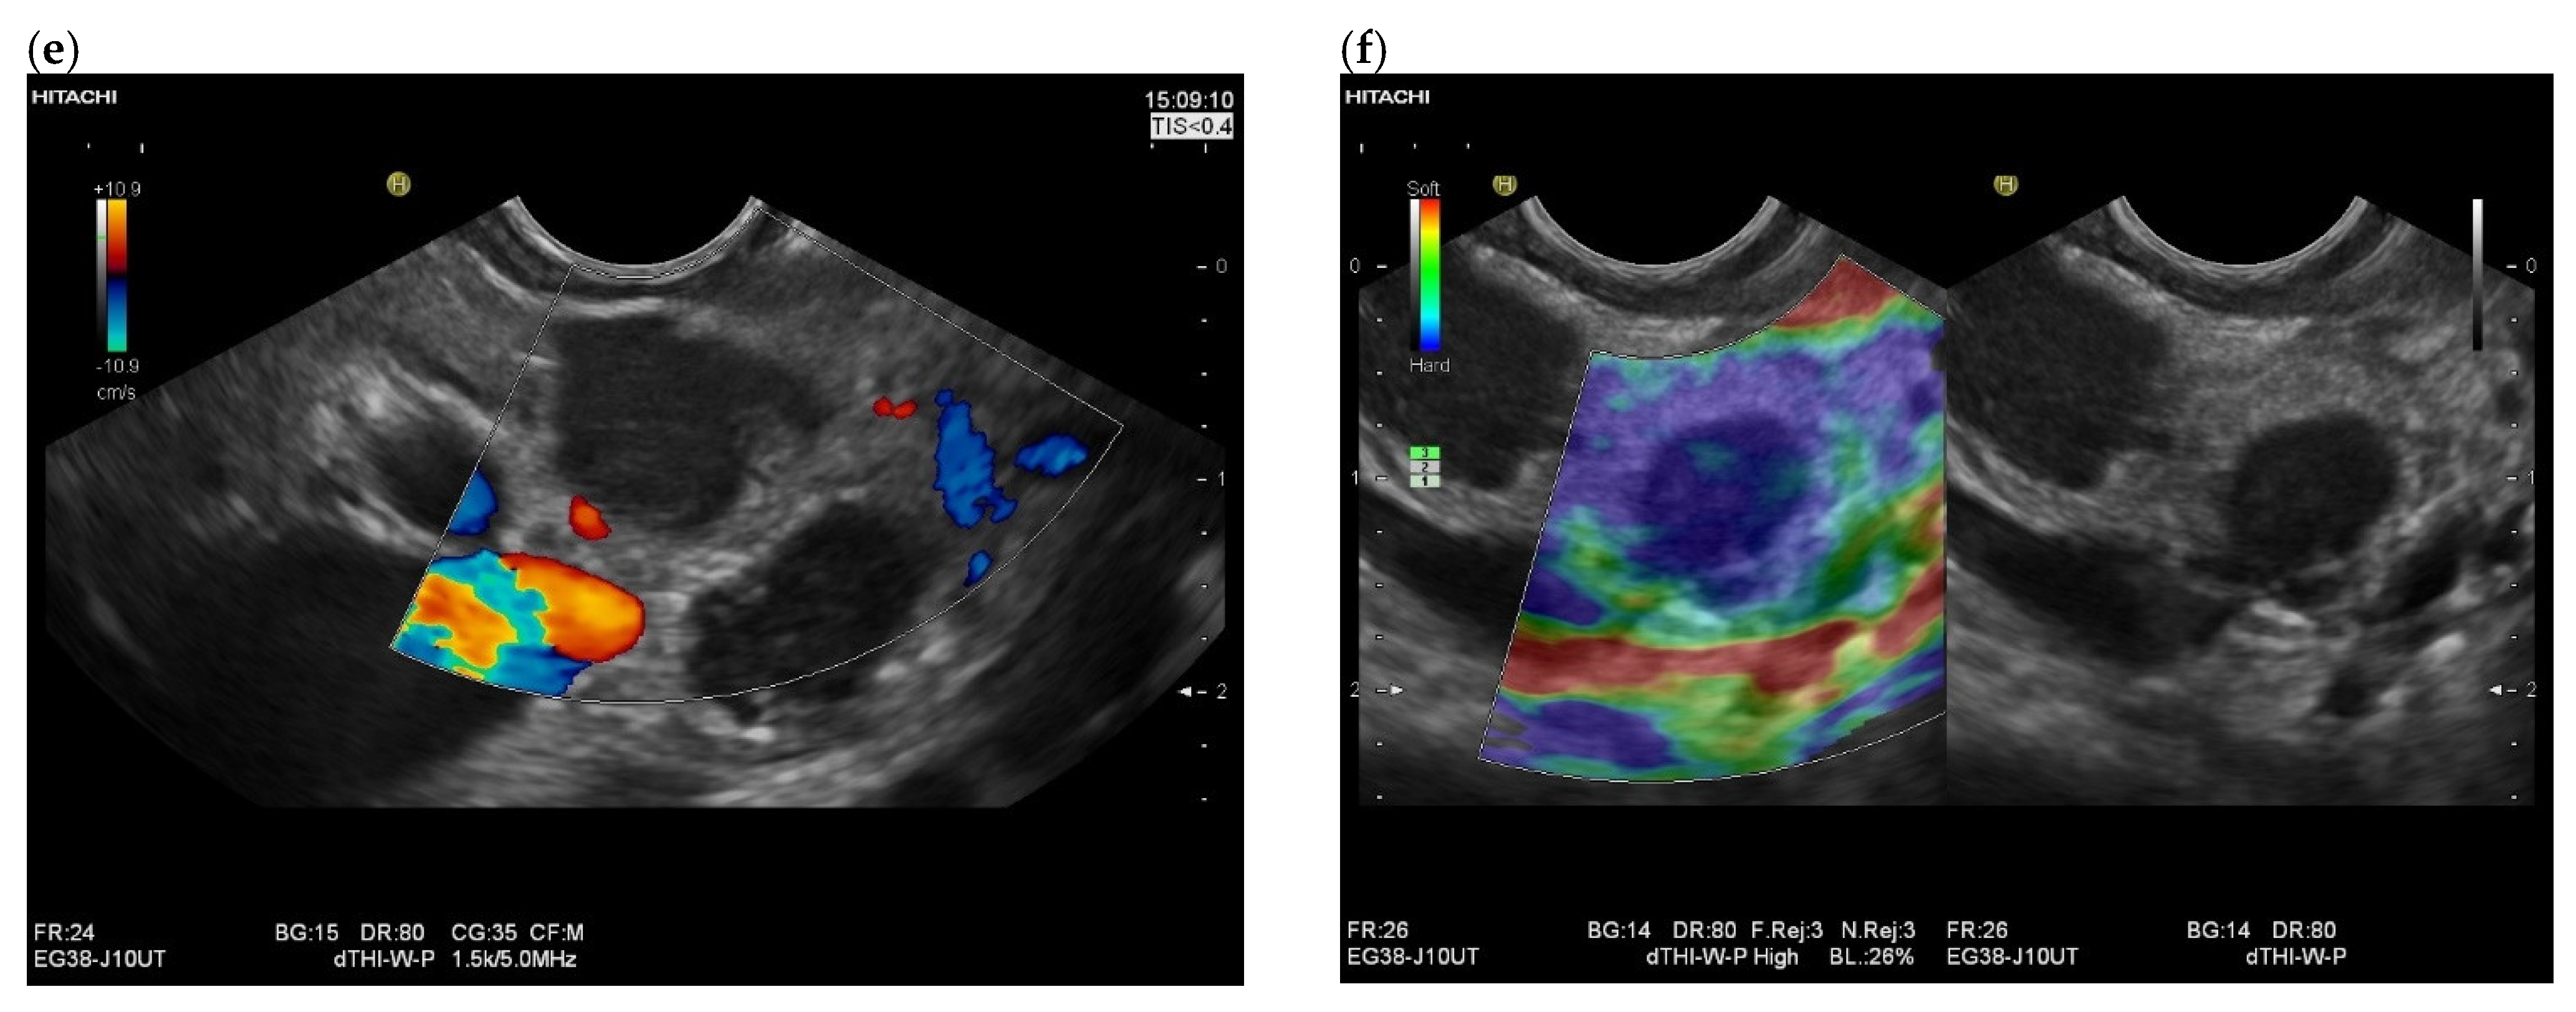

3.4. CEUS and CH-EUS

B-mode US/EUS

| Mostly hypoechoic, homogeneous, or heterogeneous More likely well-defined borders (46%) Anechoic and hyperechoic lesions are possible | Hypoechoic, typically heterogeneous, irregular borders | Hypoechoic, mostly homogeneous, smoothly bordered. Cystic components or cystic solid PanNENs are possible |

| Mostly no infiltration into adjacent vessels | Infiltration around and into the vessels | No infiltration into adjacent vessels |

| Colour Doppler Imaging | RCC metastases are hypervascularized Most other pancreatic metastases are hypovascularized | No hypervascularization | Hypervascularized |

| Elastography (small lesions up to 15 mm) [67] | 41% softer or isoelastic, 59% stiffer compared to pancreatic parenchyma | 4% soft or isoelastic, 96% stiffer compared to pancreatic parenchyma | 64% soft or isoelastic, 36% stiffer compared to pancreatic parenchyma |